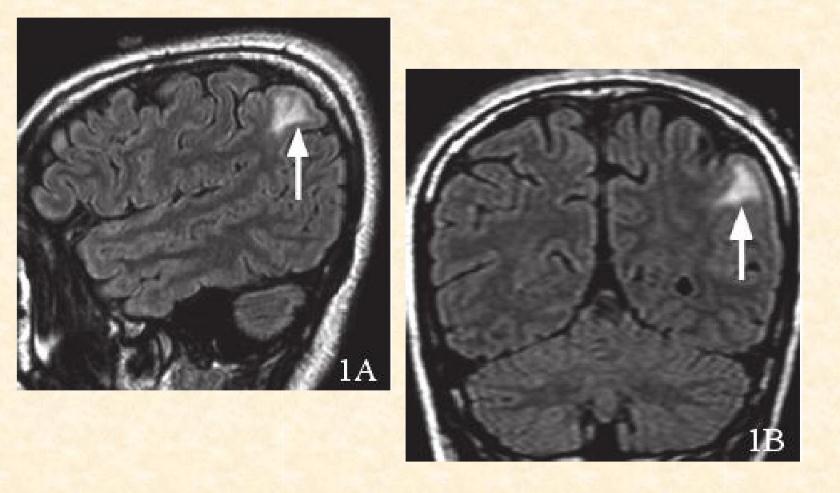

患者大脑内皮层发育异常,在磁共振下看得很清楚

跟孕期吃不吃羊肉没有关系